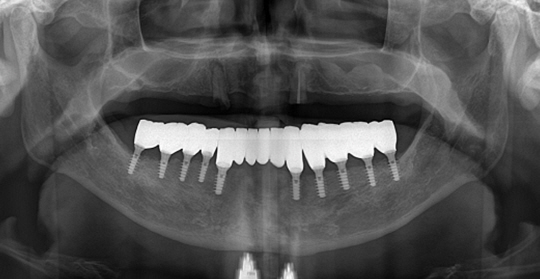

(66세 여 환자)